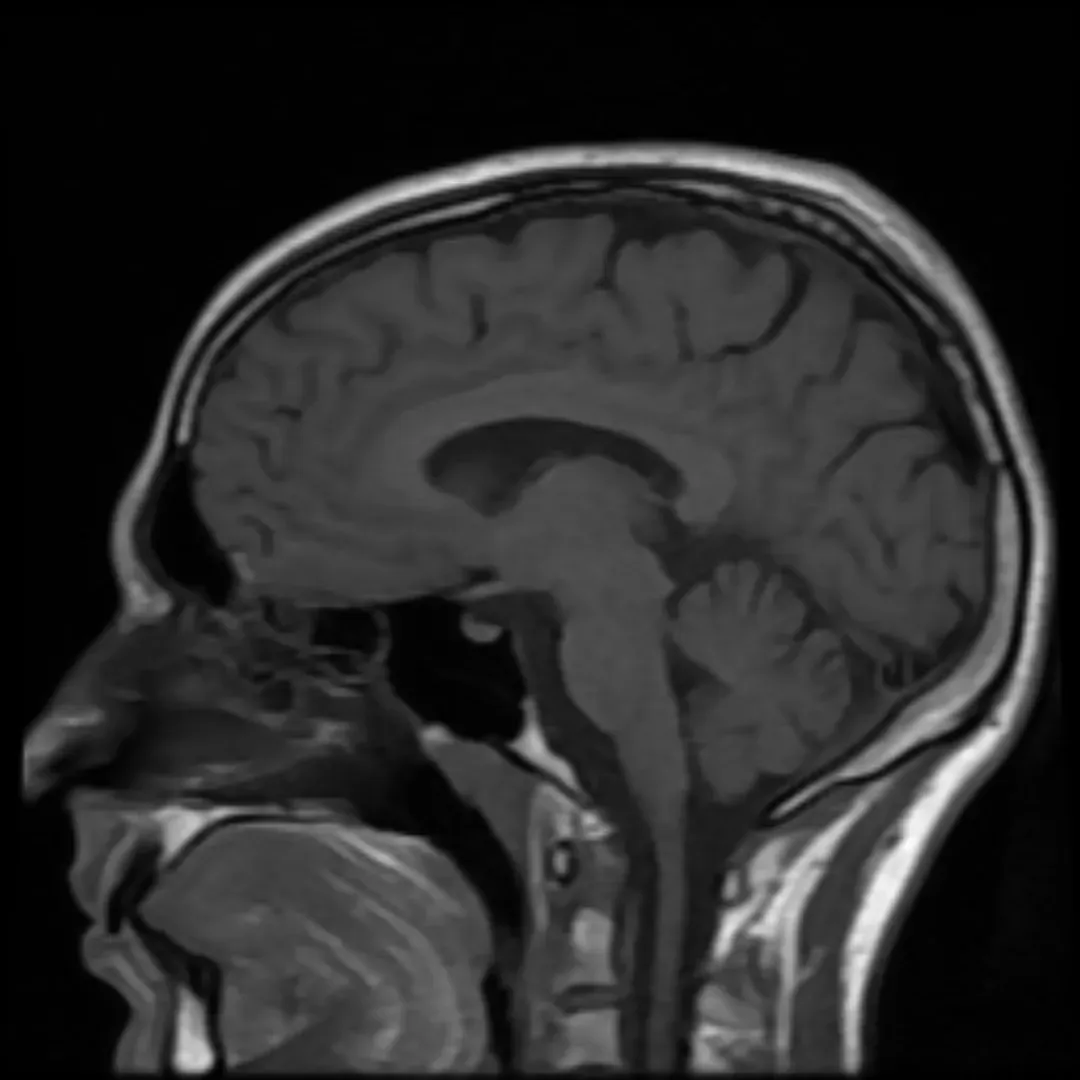

Dreams are a most remarkable experiment in psychology and neuroscience, conducted every night in every sleeping person. They show that your brain, disconnected from the environment, can generate by itself an entire world of conscious experiences. Think of it like a private cinema running a show that you did not write, starring people you may or may not recognize.

As you enter a dreamlike state, the prefrontal cortex of the brain, responsible for keeping impulses in check, slowly grows less active. This is when there is a surge in theta waves that leads to an unconstrained window of consciousness, with little censorship from the mind, allowing for visceral dreams and creative thoughts. In other words, your brain’s inner editor basically leaves the building.